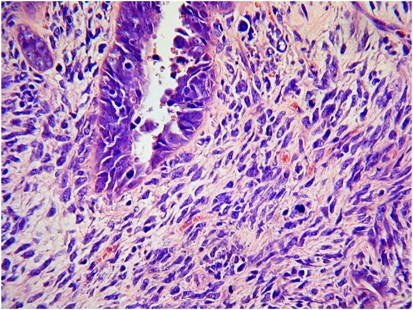

A histological diagnosis of carcinosarcoma depends on identifying high-grade malignant epithelial and mesenchymal components typically showing a sharp demarcation between both, although occasionally this demarcation may be blurred (Figure 1). The epithelial element may include serous, grade 3 endometrioid, clear cell and undifferentiated carcinoma in order of frequency. Admixtures may be seen and typing of the epithelial component may be difficult; in some cases, a hybrid morphology (with features of serous and endometrioid carcinoma) or a malignant squamous component is present (Figure 2), which may be a clue to the diagnosis. The mesenchymal component can be homologous or heterologous. The former is typically a high-grade sarcoma, NOS and eosinophilic hyaline globules are frequently noted. If heterologous elements are present, then rhabdomyoblasts or malignant cartilage is the most common. Osteosarcomatous and liposarcomatous differentiation may rarely occur (Figure 3). On occasion, carcinosarcomas are associated with a component of primitive neuroectodermal tumour (PNET); in such cases, markers such as neurofilament, glial fibrillary acidic protein (GFAP) and synaptophysin may be useful in highlighting this component, which is more analogous to a central than a peripheral PNET without EWSR1 gene rearrangement.9 Occasional examples of a yolk sac tumour component and melanocytic differentiation have also been reported.10, 11

The relative proportions of epithelial and mesenchymal components vary widely; thus, extensive sampling in an undifferentiated sarcoma or pleomorphic rhabdomyosarcoma may reveal areas diagnostic of carcinosarcoma. Uncommonly, carcinosarcomas have a low-power growth pattern, which mimics an adenosarcoma (Figure 4); however, this is usually a focal finding, there is no stromal condensation, and the epithelium and the stroma are overtly malignant at high-power magnification.